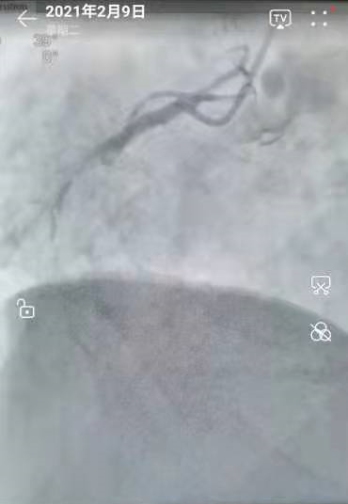

2021年2月9日,心血管内三科的医生们,在导管室正常做着介入手术!今天共3个患者。最后一台是一个胸痛的病人,造影:右冠闭塞99%。与家属沟通后,我们积极地做了开通血管的介入手术。

导丝通过顺利——球囊扩张到位——安放支架成功!

手术完美!